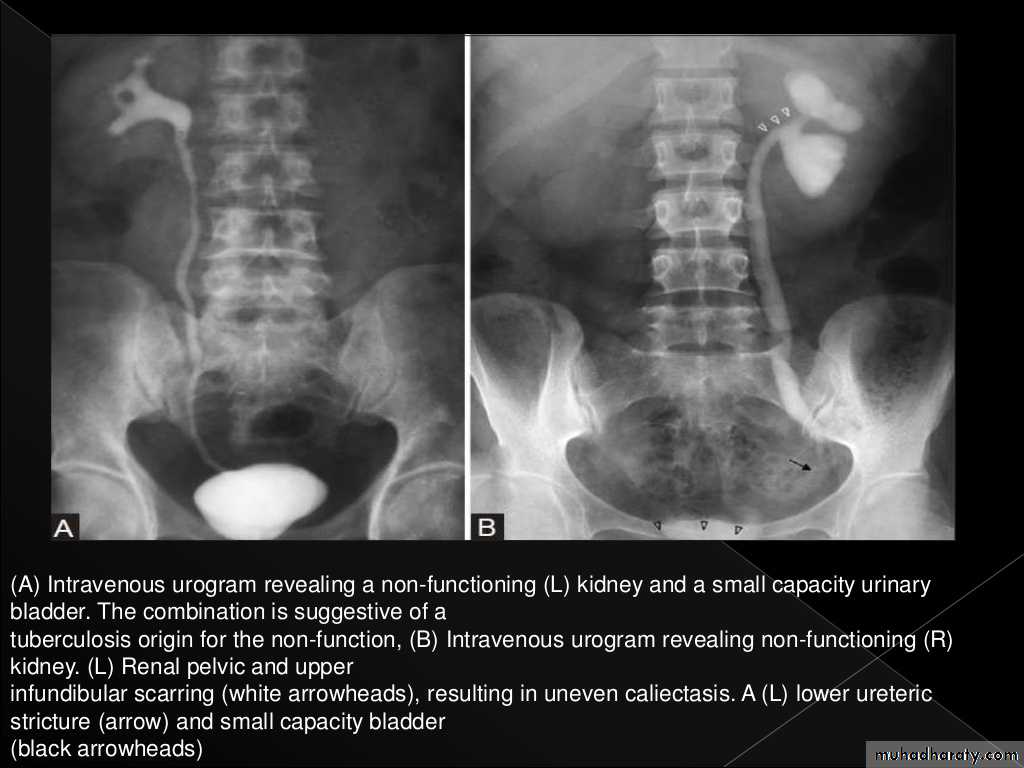

Plain films may show large globular, amorphous calcificationsIVU :

Cortical scarring

"Smudged" papillae (moth-eaten) –irregular due to inflammation and necrosis

Infundibular strictures

Hydrocalyces without dilatation of renal pelvis, or Hydronephrosis

Autonephrectomy – small, shrunken kidney with dystrophic calcification

When ureters are involved, usually the upper or lower third (more common)

Bladder involvement rarely leads to calcification of wall (think schistosomiasis)